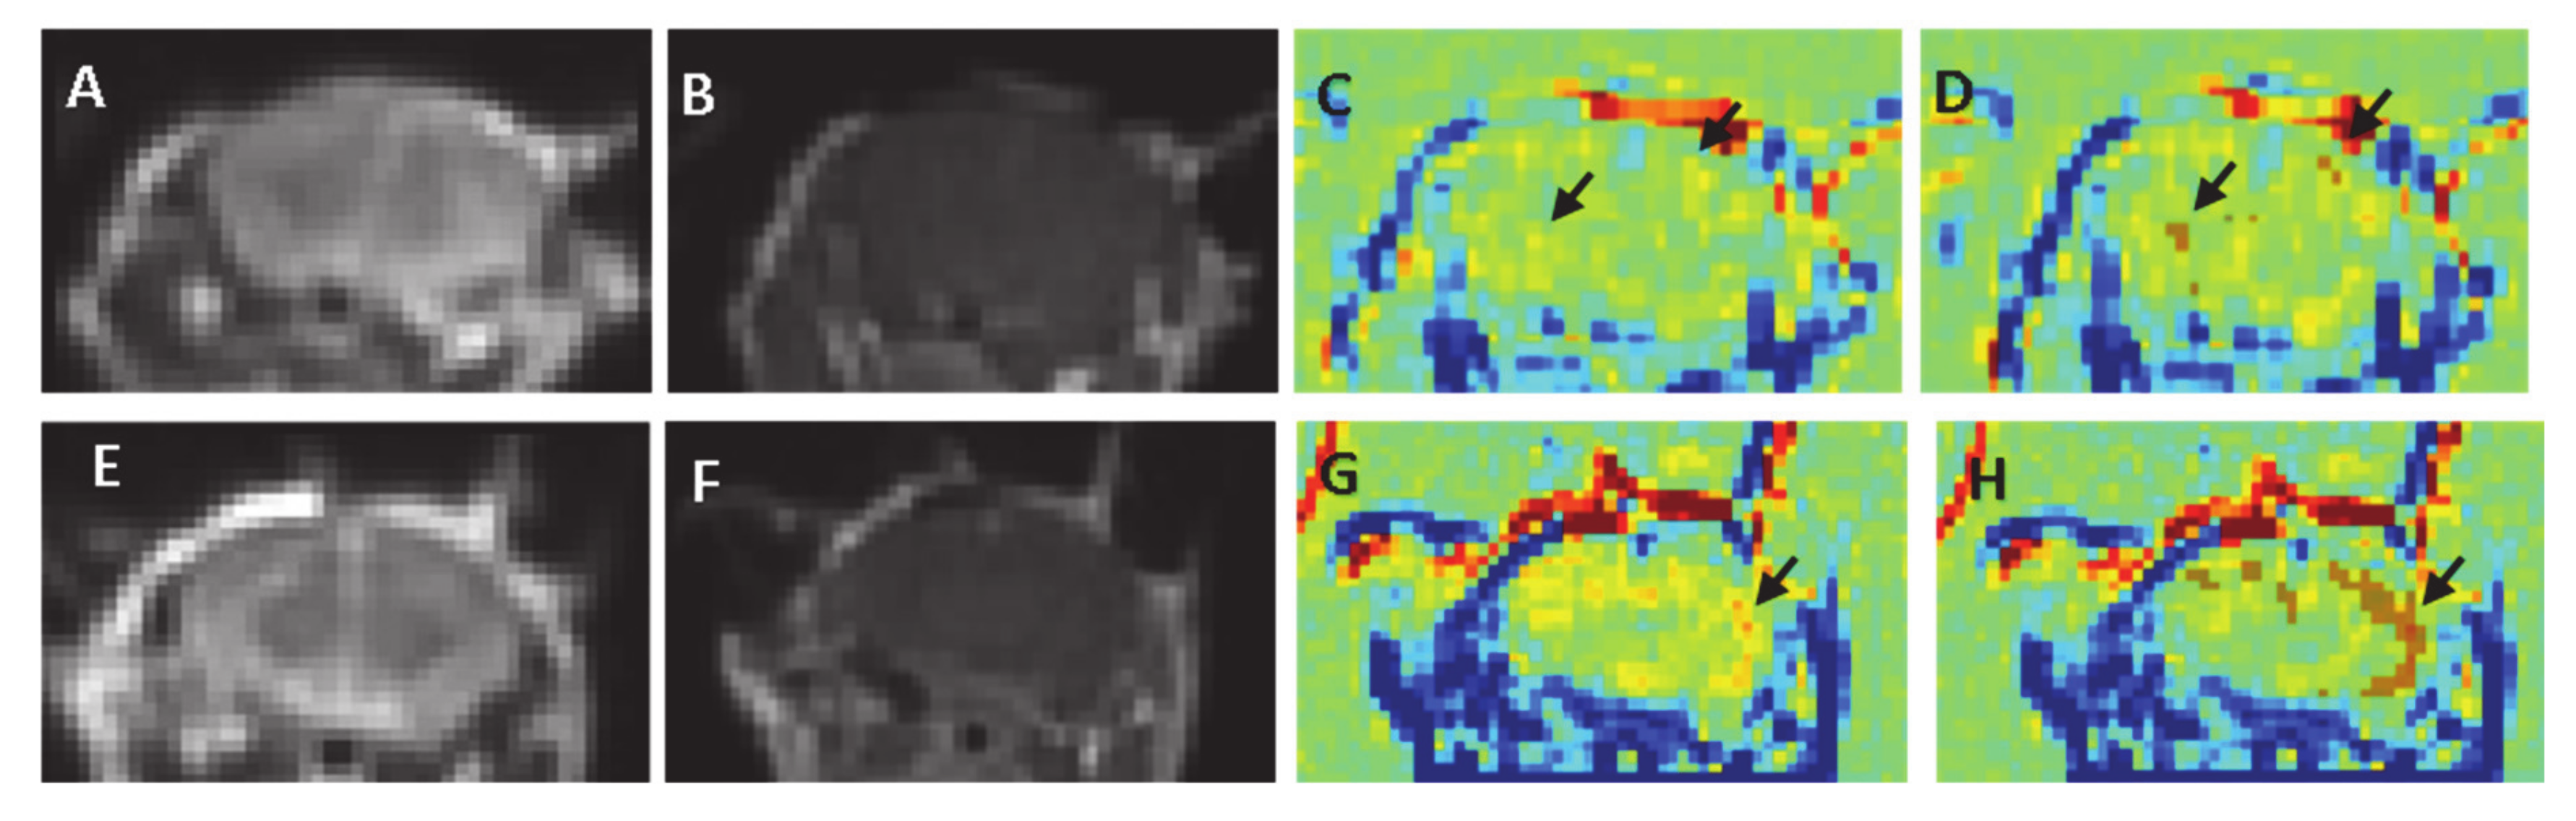

Figure 3.

MRIs of a sham mouse and a mouse from the 100 V, 100 pulses group (A–D). Sham, (E,F). 100 V, 100 pulses (A) + (D). Table 2. MRIs showing no signs of damage or edema (B) + (F). Contrast-enhanced T1-MRI showing no visible enhancement in the brain parenchyma. (C) + (G). TRAMs calculated by subtracting the first T1-MRI from the 30 min T1-MRI. No clusters of contrast accumulation are visible in the sham mouse ((C), arrow shows scattered pixels), while contrast accumulation is visible in the cortex (arrow) of the treated mouse (G). (D) + (H) The results of the analysis algorithm showing random small clusters in the sham brain (brown pixels) and significant BBBd clusters (mainly in the cortex) in the treated mouse.

No signs of edema, damage or bleeding were observed in any of the treated mice. Standard 3D T1-MRI obtained immediately post-contrast injection showed no clear enhancement in the brain parenchyma in any of the mice (Figure 3A,B,E,F). Nevertheless, the calculated TRAMs, which are sensitive to subtle BBBd, reveled significant BBBd which increased with the treatment voltage and with the number of pulses. The TRAMs showed contrast agent accumulation (depicted red) mainly in the cortical region, as predicted by the simulation (Figure 3G–H). The average volume of BBBd found for the sham group (0 V) was 6.08 ± 3.09 mm3 and the average intensity increase was 6.76% ± 0.2%. The pixels determined to represent BBBd by our analysis algorithm were sporadic pixels scattered in the brain resulting from noise. The average BBBd volume of the minimal treatment group (100 pulses at 100 V) was significantly larger than that of the sham group (39.10 ± 9.66 mm3, p < 0.02) and the disrupted volume was concentrated mainly in the cortex of the mice, as can be seen in Figure 3. The increase in signal intensity was also significantly higher than that of the sham group (13.73 ± 4.09, p < 0.009). These results suggest that subtle BBBd was obtained when applying 100 pulses at 100 V.